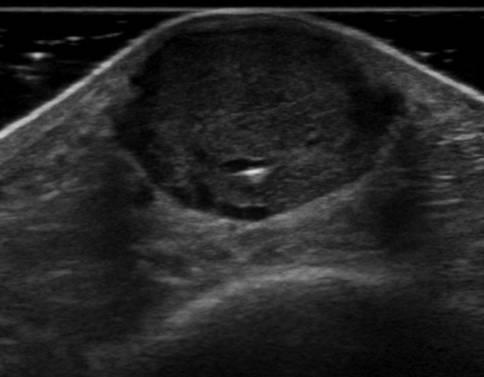

U máu

U máu - Ảnh 3

» Thông tin: Nam giới – 66 tuổi.

» Lâm sàng: Sưng cẳng chân.